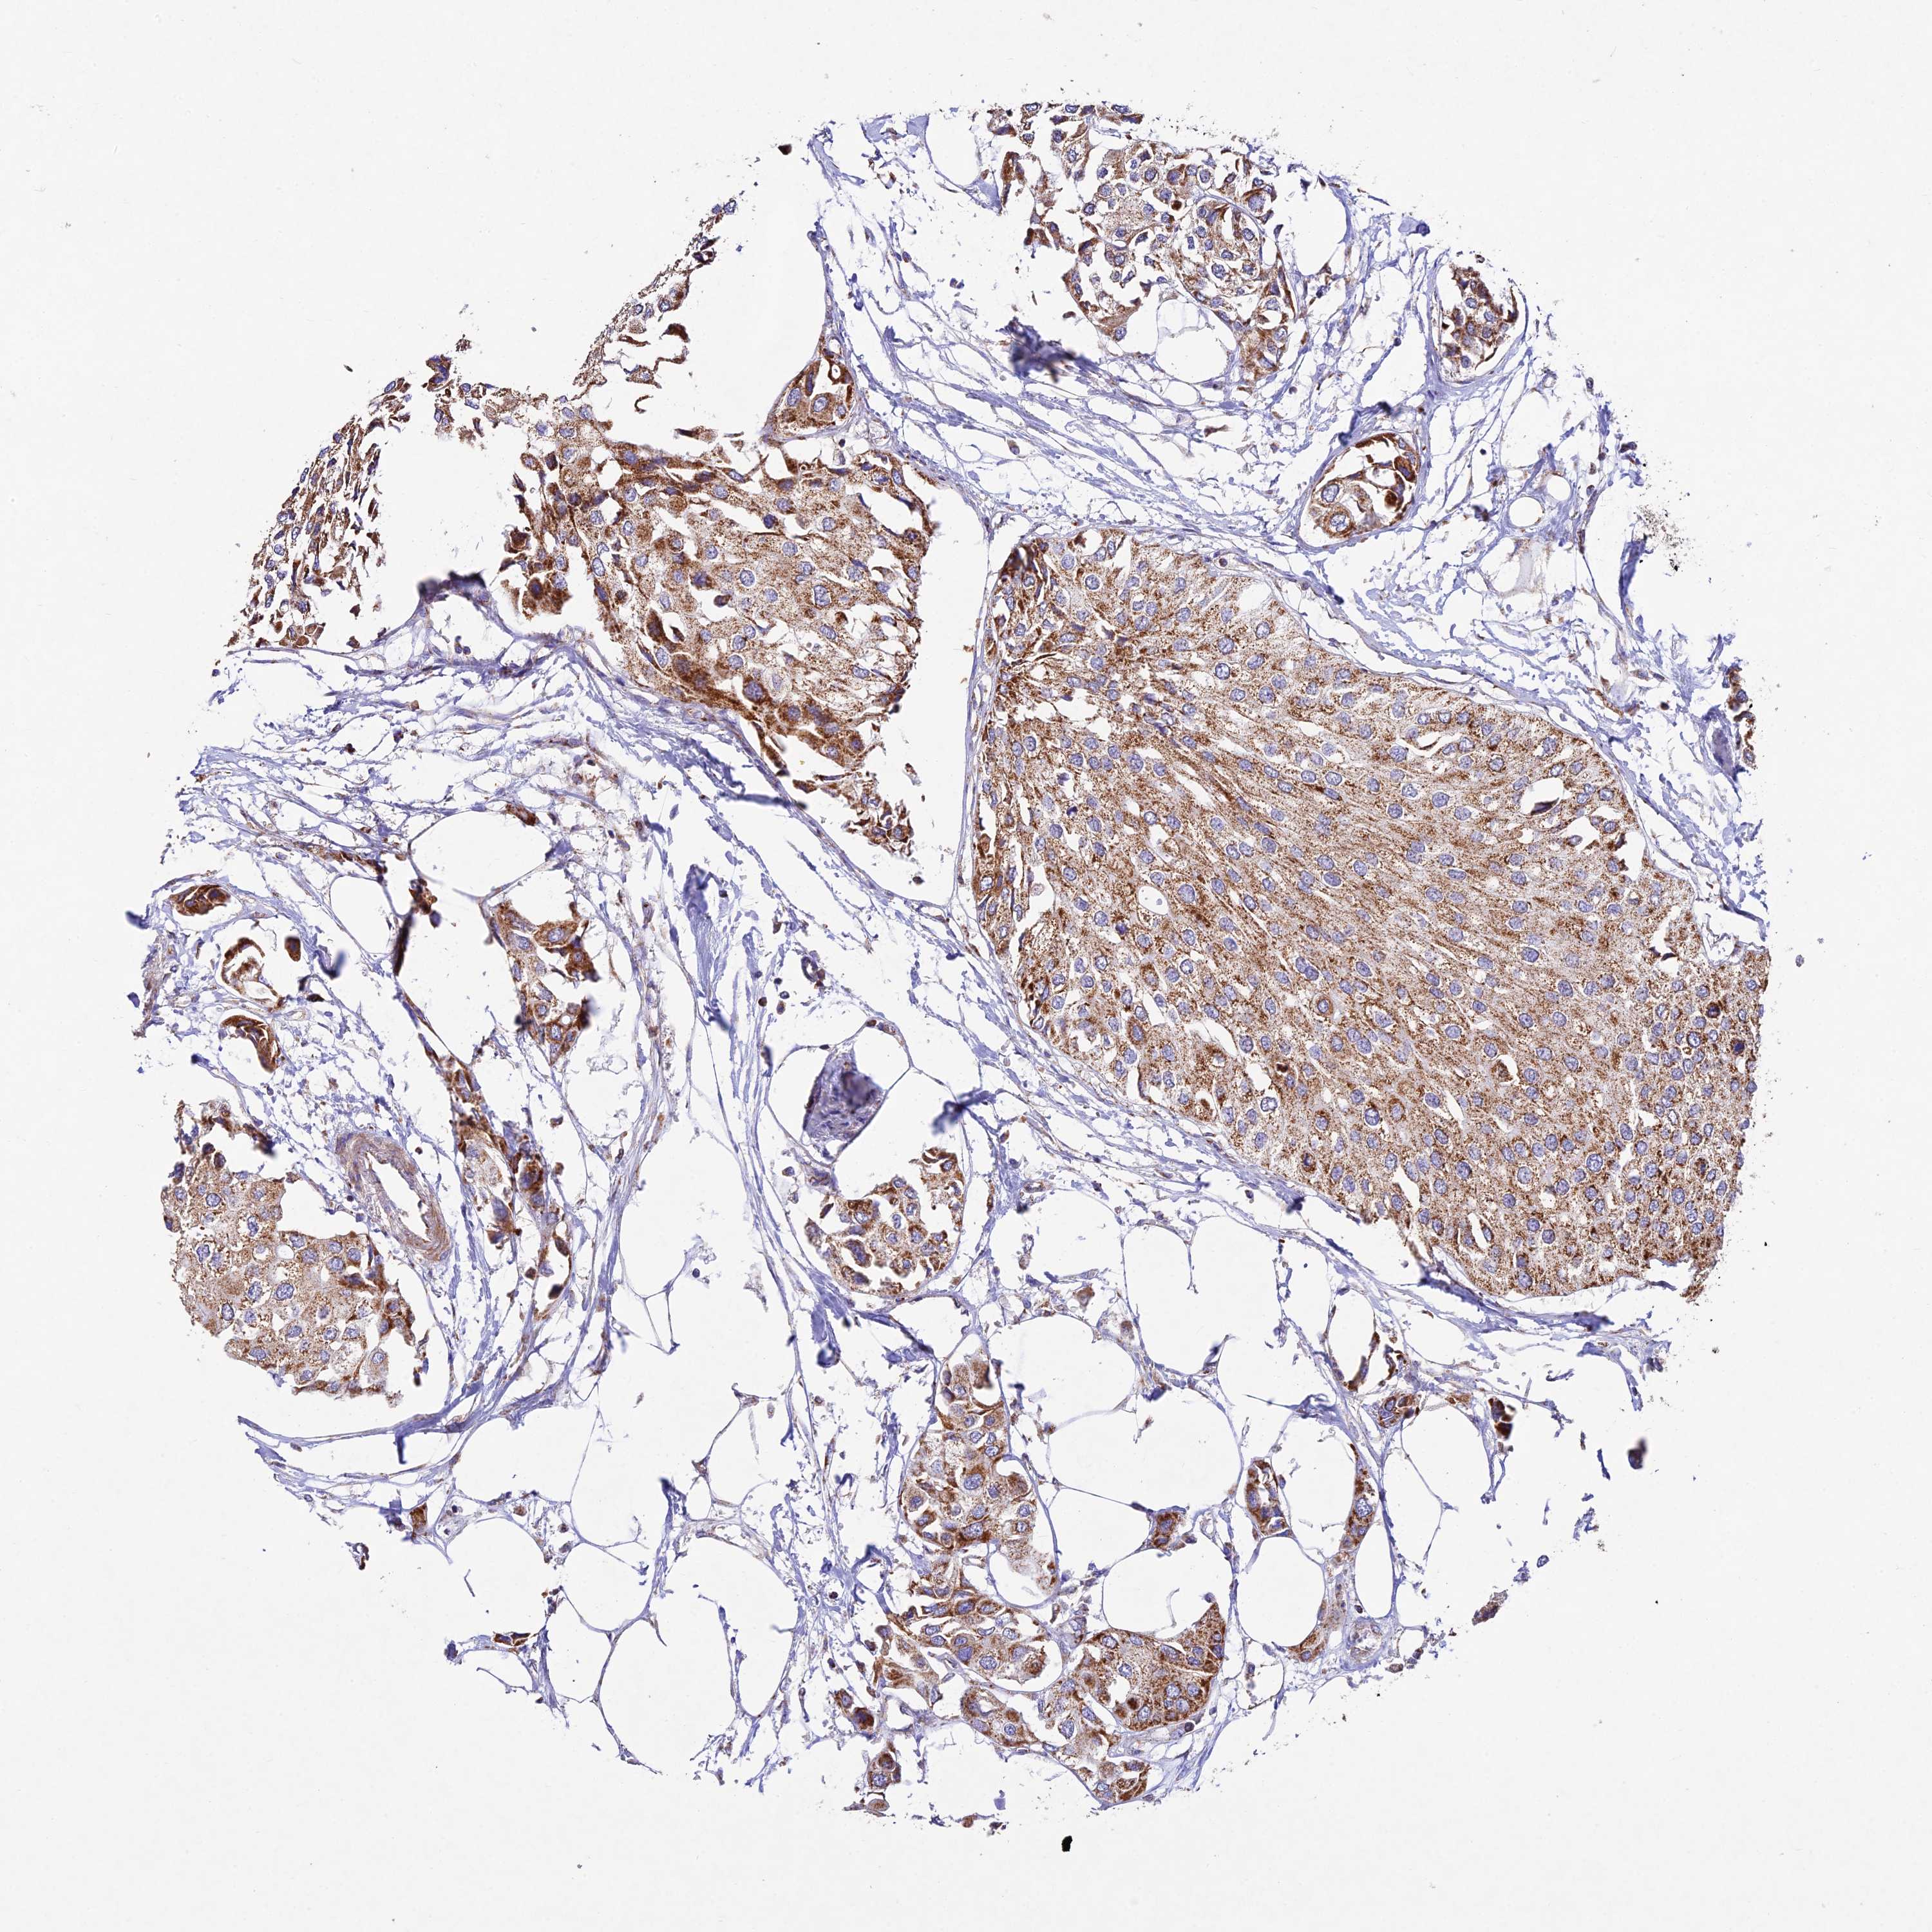

UROTHELIAL CANCER - Protein expressioni

A mouse-over function shows sample information and annotation data. Click on an image to view it in a full screen mode. Samples can be filtered based on level of antibody staining by selecting one or several of the following categories: high, medium, low and not detected. The assay and annotation is described here.

Note that samples used for immunohistochemistry by the Human Protein Atlas do not correspond to samples in the TCGA dataset.

Antibody stainingi

Antibody staining in the annotated cell types in the current human tissue is reported as not detected, low, medium, or high, based on conventional immunohistochemistry profiling in selected tissues. This score is based on the combination of the staining intensity and fraction of stained cells.

Each image is clickable and will lead to virtual microscopy that enables deeper exploration of all samples and also displays staining intensity scores, fraction scores and subcellular localization as well as patient and tissue information for each sample.

Antibody HPA043699

Staining

High

Medium

Low

Not detected

Intensity

Strong

Moderate

Weak

Negative

Quantity

>75%

75%-25%

<25%

None

Location

Nuclear

Cytoplasmic/membranous

Cytoplasmic/membranous,nuclear

Urothelial carcinoma, High grade

Urothelial carcinoma, Low grade